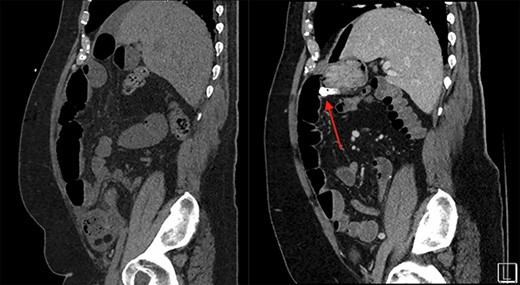

On the left is the initial CT scan non-contrast demonstrating no obvious mass. On the left is the CTA, a week later, showing a mass and pill cam in the right upper quadrant.

The patient is a 69-year-old male with a past medical history of hypertension, chronic kidney disease, chronic obstructive pulmonary disease, right renal cancer status post-laparoscopic nephrectomy in 2016 (pathology showed renal cell carcinoma with invasion into the adrenal gland, Fuhrman nuclear grade 3–4, pT4 pN0, Stage IV) who presented to the emergency room (ER) with abdominal pain. The patient recently underwent an esophagogastroduodenoscopy and a colonoscopy the week prior as a workup for anemia, which were unremarkable. Since then, he started having intermittent abdominal pain and bloating. The CT abdomen and pelvis without contrast in the ER showed multiple dilated small bowel loops with a transition point in the right lower quadrant (Figs 1 and 2). Due to his history of previous abdominal surgery, this was diagnosed as a small bowel obstruction secondary to adhesions. He was initially managed with a nasogastric tube and gastrografin study. On hospital Day 1, he had minimal output from his nasogastric tube and started to have bowel movements; therefore, his nasogastric tube was removed and he was started on a liquid diet. His diet was advanced, and on hospital Day 2, the patient was discharged.

The next week, unbeknownst to his Gastroenterologist about his recent small bowel obstruction admission, he then proceeded with a capsule endoscopy study to assess for other causes of his anemia. He tolerated the pre-operative bowel preparation without issues. After swallowing the capsule, he subsequently had bloody bowel movements. He then went to the ER and found to have a hemoglobin of 7.1, which was decreased from his prior week’s hospitalization, 8.4. A CT angiography (CTA) abdomen and pelvis was then performed that showed a 4 × 6 × 4.1 cm mass in the right upper quadrant with the capsule endoscopy at the level of the mass (Figs 1 and 2). The images from the capsule were unremarkable. On review of his imaging with radiology, it appeared that this mass was not apparent without IV contrast on his previous CT scan a week prior. In addition, a prior CT abdomen pelvis with IV contrast 10 months ago was negative for a small bowel mass. A repeat abdominal and pelvis CT with oral and IV contrast was done for confirmation. This re-demonstrated the 6 cm mass with the capsule stuck proximal to it; therefore, we performed a diagnostic laparoscopy.